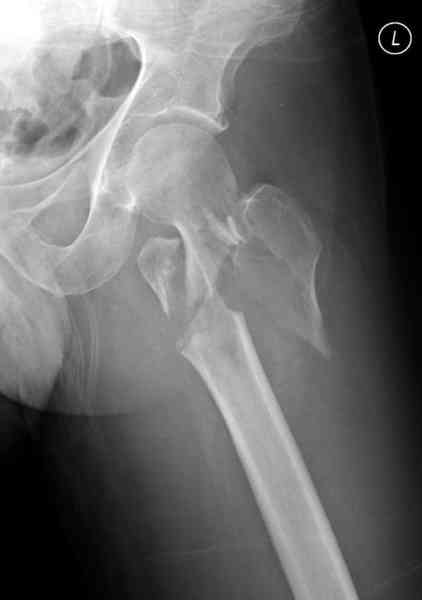

[1/3] Перелом проксимального бедра

Представляю случаи повреждения проксимального отдела бедра. Все три поступили сегодня по дежурству:

N1 больному 41, травма в результате автоаварии, взяли на скелетное вытяжение, по поводу перелома зуба С2 позвонка без смещения на Halo fixation.